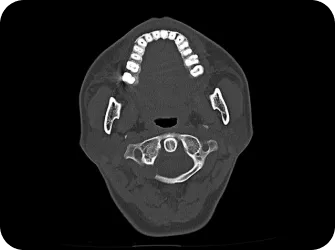

척추 엑스레이 검사

족부 엑스레이 검사

다리길이 엑스레이 검사

모아레 근육 균형 검사

상부경추 1,2번 CT

적외선 체열검사